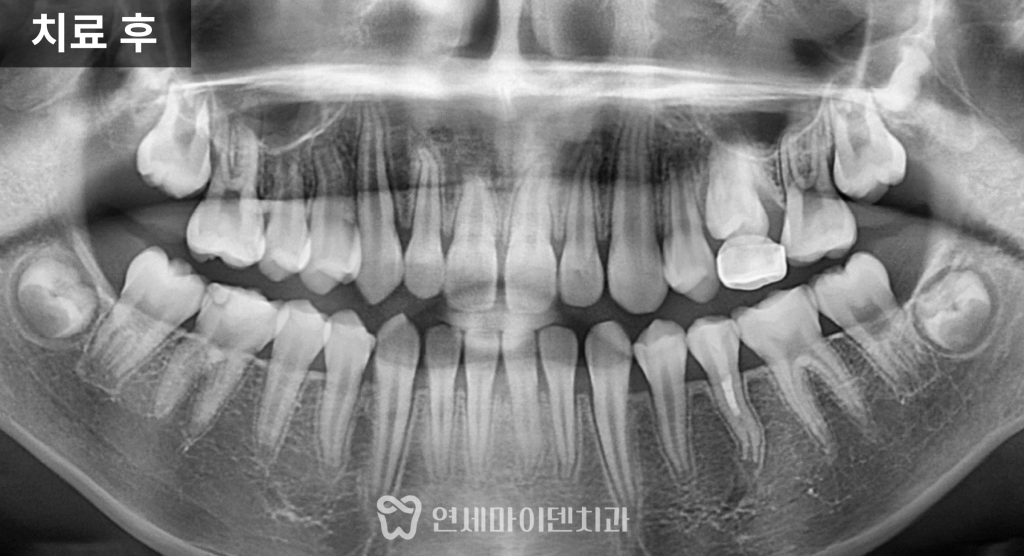

치료 후 가장 먼저 확인된 변화는

치아의 흔들림이 사라졌다는 점입니다.

이후 경과를 관찰한 결과

3년이 지나면서

뿌리 길이가 점차 늘어나고

두께도 함께 증가한 모습이 확인되었습니다.

이는 치근단 형성술을 통해

뿌리 성장이 정상적으로 진행되었다는 의미입니다.

결과적으로

발치 없이 자연치아를 유지하면서

장기적으로 사용할 수 있는 기반을

마련한 케이스입니다.